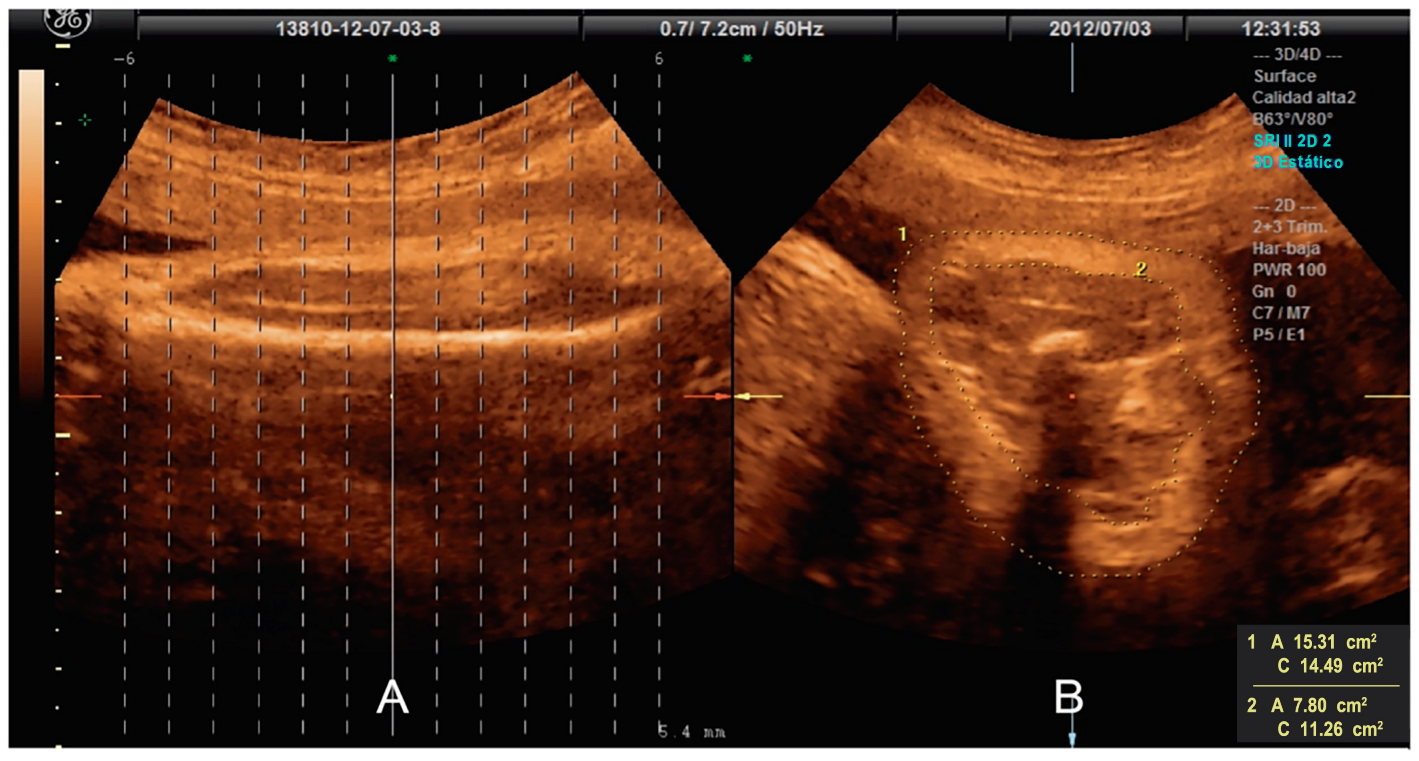

2.4. Assessment of Fat Mass Area